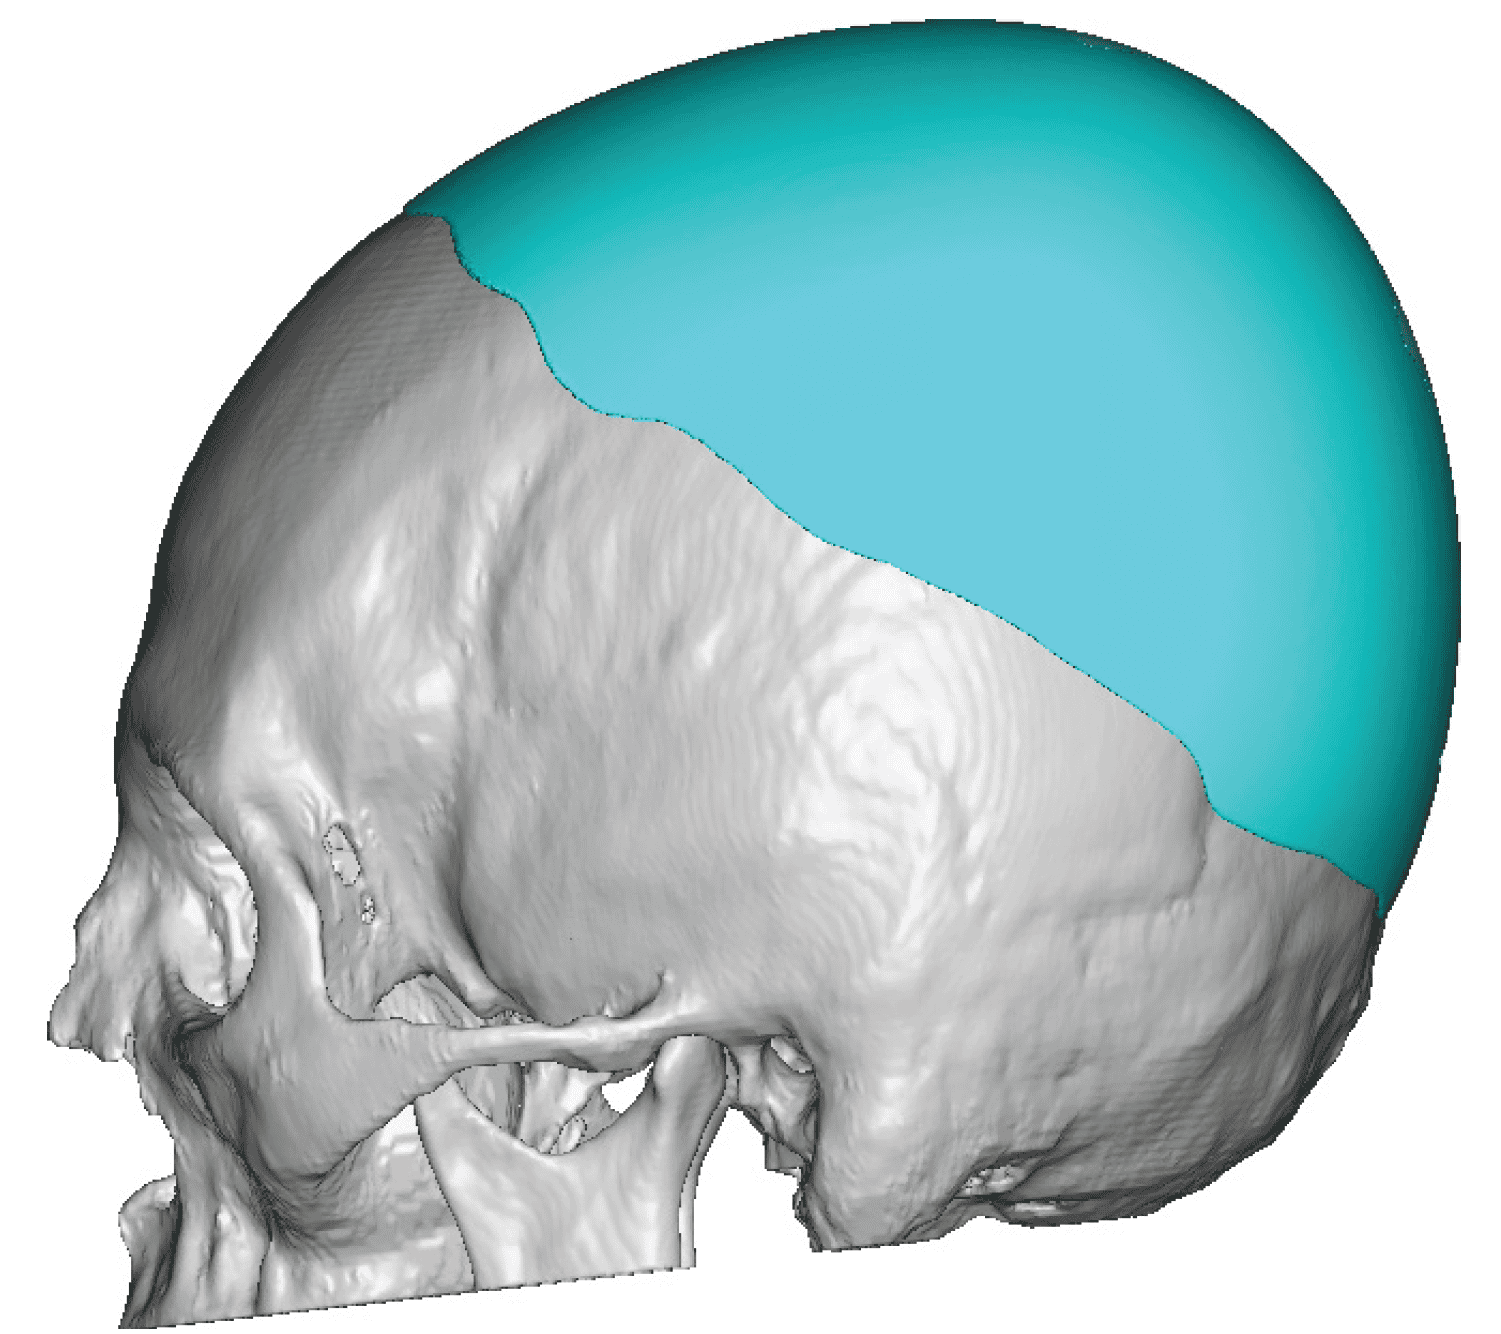

Patient 28

Desire for rounder shape to the top of the head from a congenital parasagittal deficiency skull shape.

Custom skull implant designed to fill in the parasagittal deficiencies.

Desire for rounder shape to the top of the head from a congenital parasagittal deficiency skull shape.

Custom skull implant designed to fill in the parasagittal deficiencies.